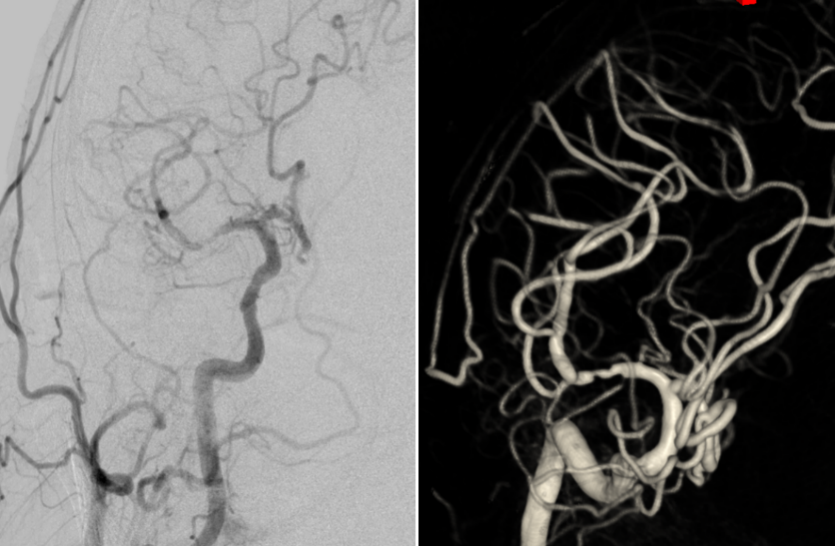

DSA:右侧大脑中动脉M1段管壁不规则溃疡斑块形成,局部重度狭窄

MRI平扫+增强:右侧大脑中动脉M1段远端不稳定斑块并管腔重度狭窄